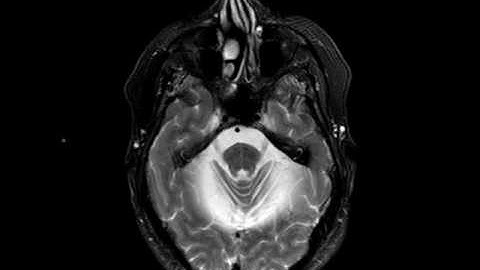

Smovey's and Multiple System Atrophy (MSA)